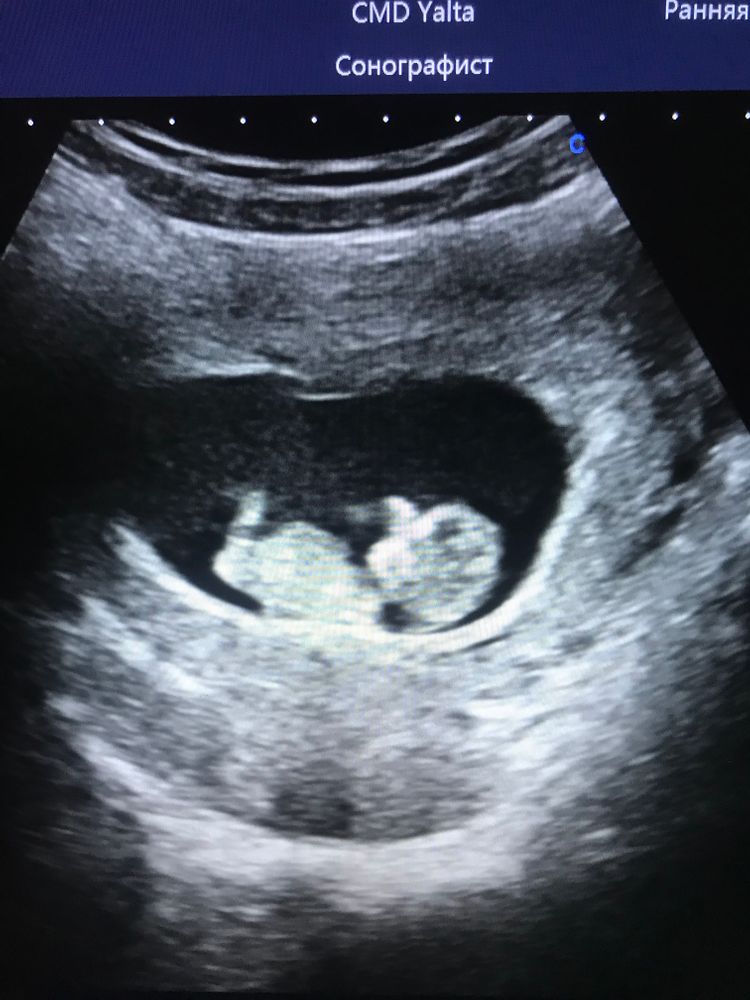

10-11 недель малыш/ка???

Девочки, ходили на прошлой неделе на 1-й скрининг, врач проводить отказалась, тк ребёнок слишком мал КТР 46, но это муж услышал, я где-то в мониторе витала 🤪. У меня поздняя овуляция из-за нестабильного цикла после недавних родов, гиня тоже ставит на 1-2 недели меньше срок по осмотру. В общем назначили прийти через 1,5 недели - подрастить 🥰. Странный узист ничего смотреть не стала, но сходу предположила пол - девочка 👧🏻. А у меня интуиция на мальчика. В прошлую беременность сработала - знала, что малышка, узисты на разных узи называли то один, то другой пол 🤦♀️. А вы что видите, интересно? Поделитесь мнением ☺️

Ну, вижу девочку по бугорку, но всё может измениться, сами понимаете))